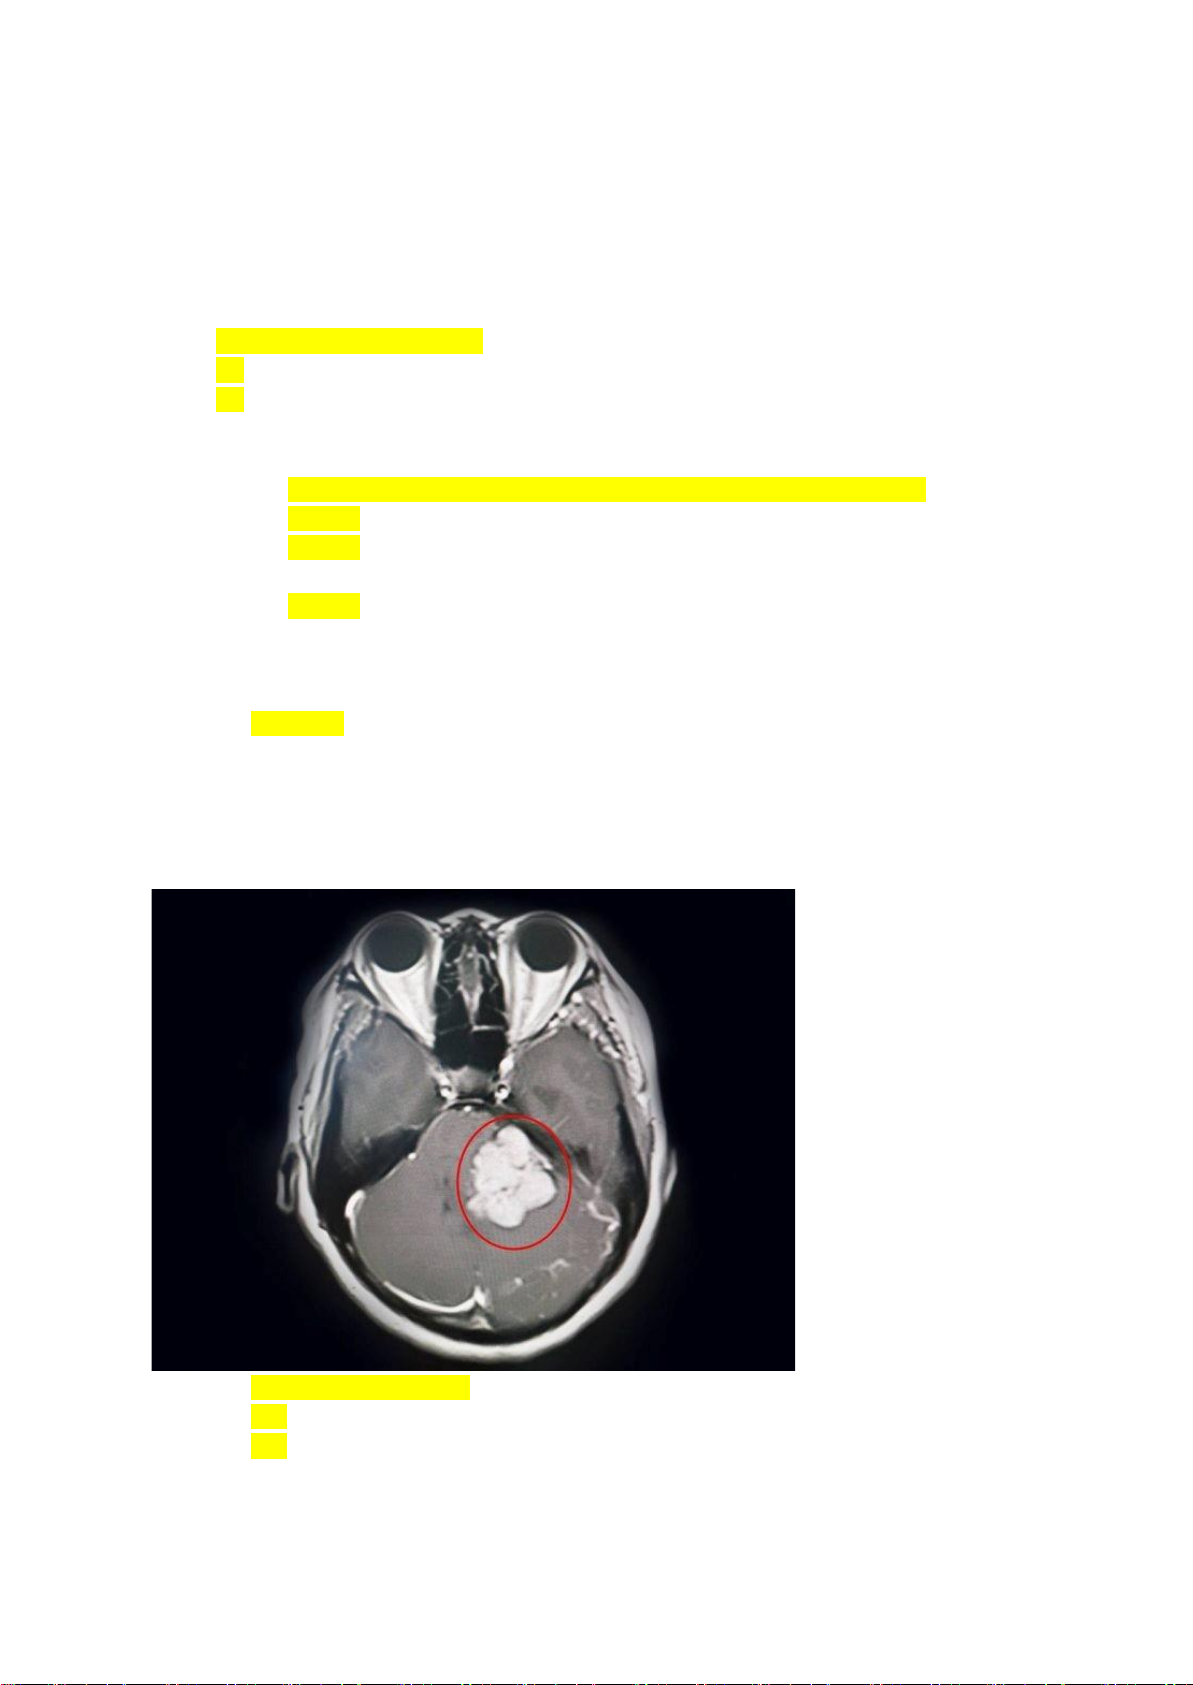

Bệnh nhân kích thích đau thì mở mắt, không nói chuyện, co nhẹ tay chấm Glasgow A. 7 điểm B. 8 điểm C. 9 điểm D. khưm nhớ Câu 10: LS + Cho hình CT hỏi A. U góc cầu tiểu não B. U thùy thái dương C. Xuất huyết

(đại loại vậy á chứ k nhớ chính xác)

Câu 11: Tiếp câu trên, dây thần kinh nào bị ảnh hưởng khi phẫu thuật: lOMoAR cPSD| 47207367 Câu 12: